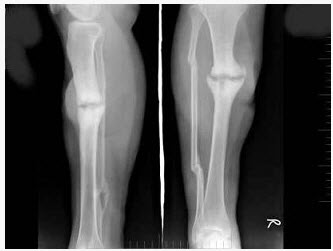

[单选题]女,48岁,车祸致右胫腓骨骨折,外固定术后两年复查,如图所示,最可能的诊断是()A .右胫骨愈合延迟B .右胫骨假关节形成C .右胫骨骨折愈合好,有大量骨痂形成D .右胫骨断端不连E .以上均不正确